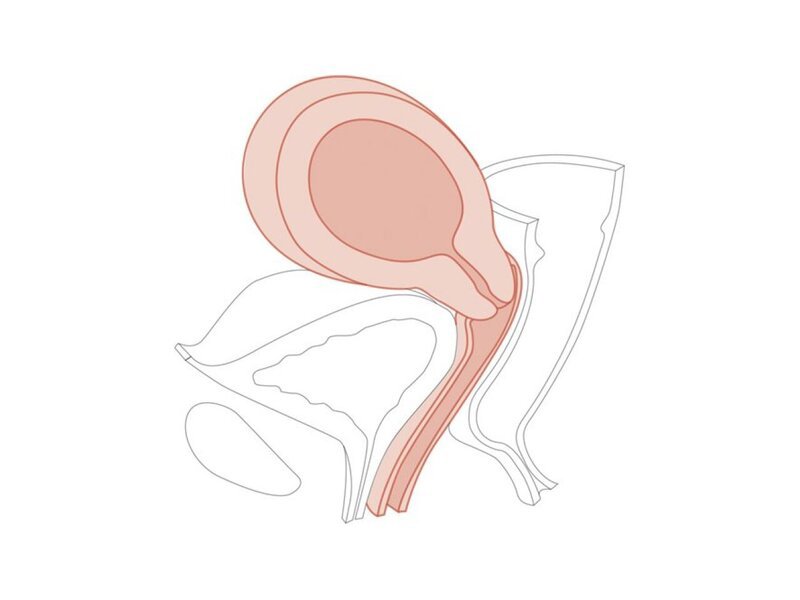

CFPT Mod 6:10-12 weeks Pregnant Cervix

Pregnant Cervix

Clinical Female Pelvic Trainer Mk 3 (CFPT): Module 6

10-12 weeks pregnant module for use with CFPT Mk3 Advanced (LIM-60905) and Standard (LIM-60900).